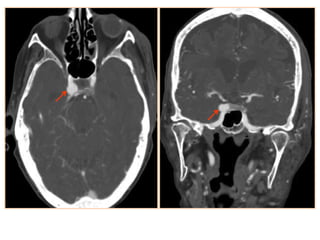

• #19 Carotid-Cavernous (C-C) Fistula. Enlarged right superior ophthalmic vein with early arterial enhancement of the right cavernous sinus suggestive of carotid cavernous fistula

• #20 Carotid-cavernous fistula: axial T2-wi (a) of a carotid-cavernous fistula appearing as a heterogeneous signal with flow voids of the right cavernous sinus (black arrows). Note the dilatation of the superior ophthalmic vein (dotted arrow) and the carotid-cavernous fistula (white arrow) on an arterial TOF of another patient with a carotid-cavernous fistula (b)